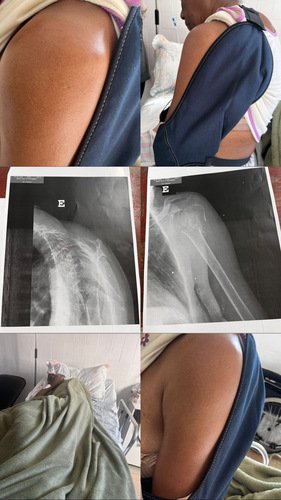

Sou conhecida por conta do meu trabalho como cabeleireira, sofri acidente no dia 30 de maio de 2025 cair na minha residência, quebrei o ombro estou há 7 dias no HPS esperando uma vaga de cirugia pois meu caso somente cirurgia não consigo vaga em nenhum hospital , estou com muita dores e única coisa que está sendo feita no momento é medicação para aguardar cirurgia mas quando passa o efeito as dores aumentam . Com ajuda dos meus filhos estou criando essa vaquinha para realizar cirurgia no particular , pois todos hospitais com convênio no sus informou que não tem vaga e todos dias estão rejeitando.

Intuindo dessa vaquinha é alcançar o valor para ajudar na cirurgia pois no momento não temos condições meu esposo ainda se encontra em repouso pós AVC não tem 1 mês que saiu do hospital .

Ajuda de vocês amigos e familiares será essencial para me ajudar pois devido a minha idade quanto mais tempo esperar essa cirurgia é pior .